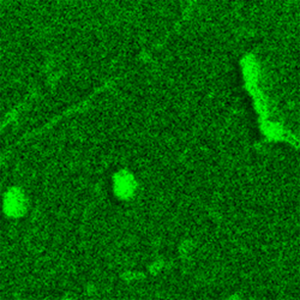

图3:TG(阿尔茨海默病)与对照(非阿尔茨海默病)样本的形貌图及1650 cm⁻¹(标记周围组织)与1740 cm⁻¹(标记磷酸化蛋白)波数PiFM图像。值得注意的是,尽管TG样本存在大量磷酸化蛋白聚集体,但两者形貌与周围组织特征仍呈现相似性。

图3展示了分别通过酰胺I带(红色,1650 cm⁻¹)标记周围组织、磷酸基团对称伸缩振动(绿色,1740 cm⁻¹)标记磷酸化蛋白的TG与对照样本形貌及PiFM图像。两样本AFM形貌高度相似,均呈现高达数微米的高度起伏特征。同样,1650 cm⁻¹波数PiFM图像显示的周围组织特征也极为相似。然而,1740 cm⁻¹波数显示的磷酸化蛋白聚集态图像则呈现显著差异:对照样本中两波数图像基本重合,表明脂质均匀分布于组织中;而阿尔茨海默病样本的1740 cm⁻¹图像不仅显示脂质/组织背景(在形貌起伏较小的中上部区域最清晰),还显现出遍布组织的大量聚集体——我们将其归因于磷酸化修饰。